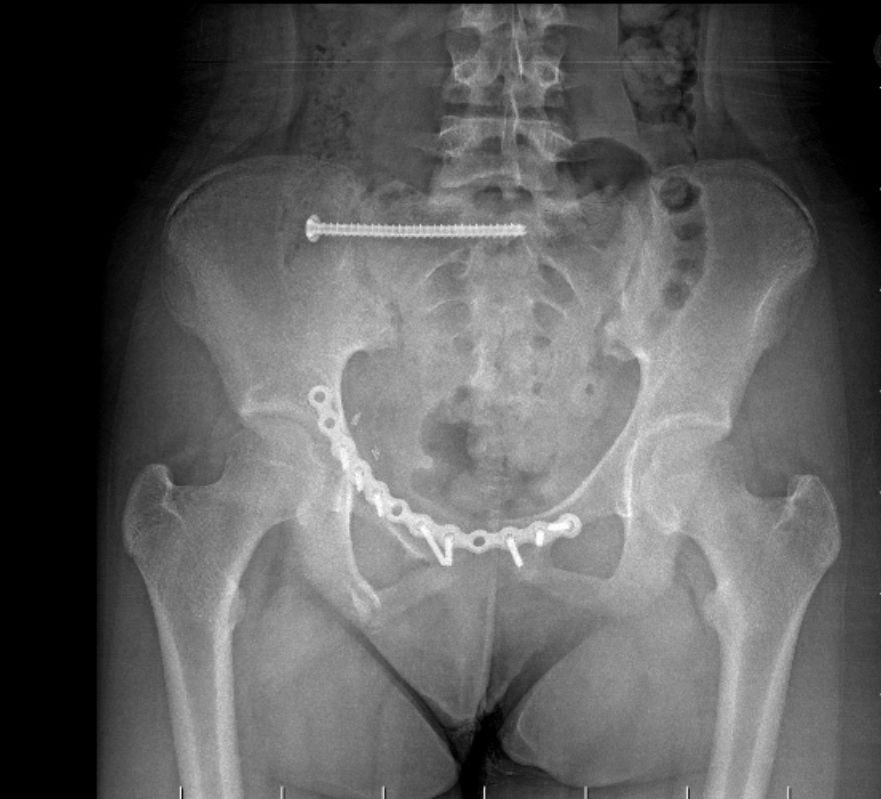

Pelvis bölgesindeki yaralanma, ameliyatı son derece riskli hale getiriyordu; çünkü kırık ve ayrışma bölgeleri ana damarlara ve mesane gibi hayati organlara çok yakındı. Op. Dr. Başer ve ekibi, bu zorlu alanda pelvis kemiğindeki ayrışma bölgesine implant yerleştirdi.

Ameliyatın en kritik kısmı ise sakrum eklemindeki ayrışmanın onarılmasıydı. Bu işlem, kapalı yöntemle ve skopi (seri görüntüleme) eşliğinde, milimetrik hassasiyet gerektiren vidalar kullanılarak başarıyla tamamlandı. Hastaneden yapılan açıklamada, kapalı yöntemle yerleştirilen vidaların yönündeki sadece 1 mm’lik bir sapmanın dahi hastada felç riski oluşturabileceği vurgulandı.